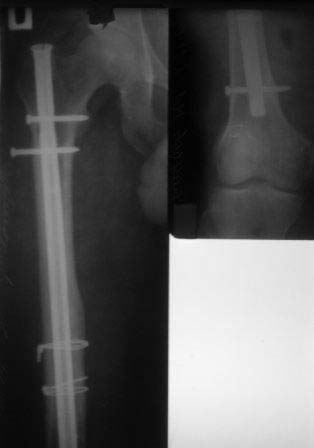

Уважаемые коллеги, обратился пациент 1978г.р. для удаления и/м  стержня из  правого бедра, оперирован в 2008 году в городе Ангарск, Иркутской  обл. Честно признаться, я не знаю такого стержня, и как его удалить, кажется, он еще сильно зажат в обл.истмуса, больной настаивает на удалении!

Если у кого есть опыт поделитесь пожалуйста!